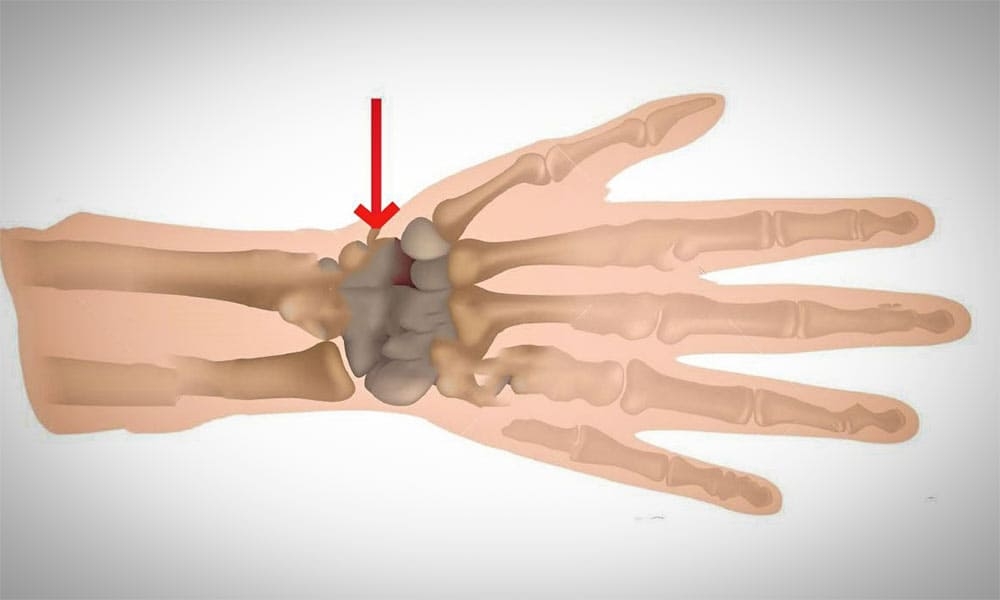

Menisküs, diz ekleminde bulunan yarım ay şeklindeki iki adet kıkırdak yapıdır. Dizde iç menisküs ve dış menisküs olmak üzere iki farklı menisküs bulunur. Bu yapılar uyluk kemiği ile kaval kemiği arasında yer alır ve diz ekleminin sağlıklı şekilde çalışmasına yardımcı olur.

Menisküsler diz eklemini koruyan önemli yapılardır. Bu nedenle menisküs dokusunda oluşan bir yırtık dizde ağrıya, şişliğe ve hareket kısıtlılığına neden olabilir.

Op. Dr. Hilmi Karadeniz, menisküslerin diz eklemi için adeta bir amortisör görevi gördüğünü ve bu yapıların zarar görmesinin diz sağlığını ciddi şekilde etkileyebileceğini ifade etmektedir.